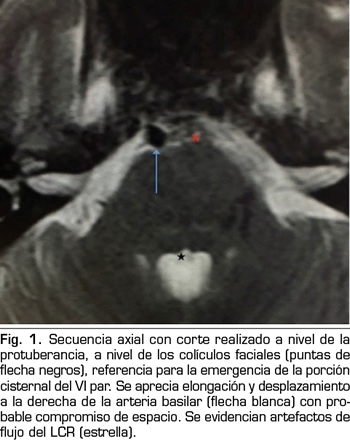

Se hace RM a los 10 días de la aparición de la diplopía objetivando un discreto agrandamiento, elongación y desplazamiento lateral derecho de la arteria basilar, con probable compromiso de espacio en la emergencia de la porción cisternal del VI par derecho (Figuras 1 y 2).

La parálisis del VI PC asociada a CPPD es un diagnóstico por exclusión que requiere la consideración de otras anormalidades neurológicas y oftalmológicas (3). Si la parálisis del VI PC ocurre dentro de las 3 primeras semanas tras la PDA y es precedida de una CPPD, es probablemente consecuencia de la PDA (4). La imagen de la RM puede revelar signos de hipotensión intracraneal, incluyendo engrosamiento meníngeo, colecciones de líquido subdurales y desplazamiento cerebral caudal (11). Estos hallazgos son debidos a la hipotensión intracraneal, sin embargo, no son específicos de la parálisis del VI PC (11). En nuestro caso, la RM no aportaba ninguno de estos signos, pero lo que sí reveló fueron datos de probable compromiso de espacio de una estructura neurológica (emergencia del VI PC derecho) por una estructura vascular (arteria basilar en nuestro caso), planteando el diagnóstico diferencial con un síndrome de compresión neurovascular. El síndrome de compresión neurovascular es definido como el contacto directo con irritación mecánica de los PC por vasos sanguíneos (7). Varios autores han comunicado casos de parálisis unilateral del VI PC, asociada con el contacto neurovascular entre el VI PC y la arteria vertebral o basilar en la RM (6).